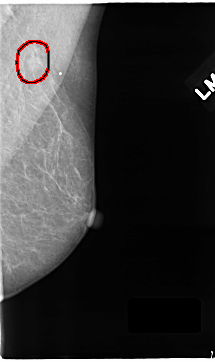

C_0122_1.LEFT_CC

LEFT_CC LINES 4712 PIXELS_PER_LINE 2560 BITS_PER_PIXEL 12 RESOLUTION 50 NON_OVERLAY

FILE: C_0122_1.LEFT_MLO.OVERLAY

TOTAL_ABNORMALITIES 1

ABNORMALITY 1

LESION_TYPE MASS SHAPE OVAL MARGINS SPICULATED

ASSESSMENT 4

SUBTLETY 4

PATHOLOGY MALIGNANT

TOTAL_OUTLINES 1